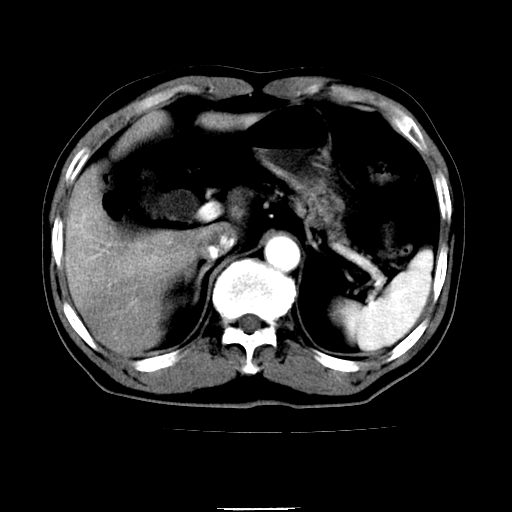

以下是引用chenqiong在2010-3-25 20:56:00的发言:[br]1、胆囊炎,胆囊息肉[br]2、肝内胆管及胆总管扩张,胆总管下端结石[br]3、十二指肠乳头旁憩室

以下是引用zxl51642在2010-3-26 10:47:00的发言:[br]胆囊炎,胆囊息肉,胆总管扩张,但未看到明显肿块,肝内胆管扩张不像恶性,炎性狭窄或阴性结石可能吧,建议mrcp,右肾小囊肿